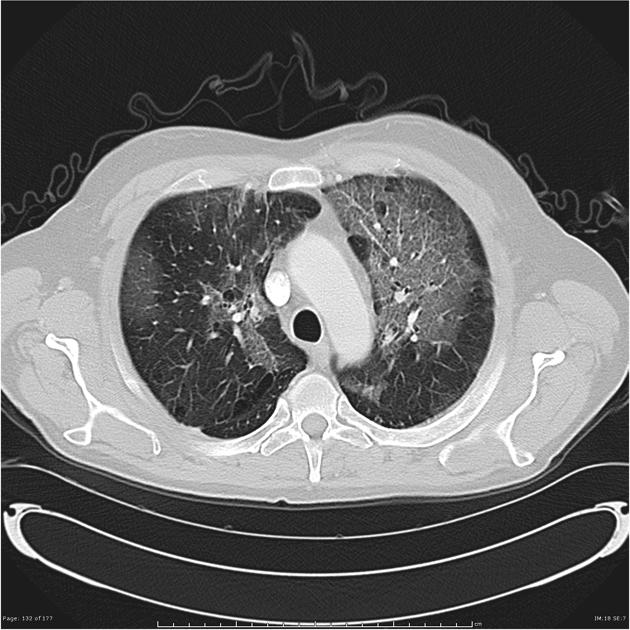

비정형 폐렴(atypical pneumonia)은 전형적인 폐렴(폐렴구균 등)과 달리, 비정형 병원체(마이코플라스마, 클라미디아, 리케차, 바이러스 등)에 의해 발생하는 폐렴을 의미한다. 독감(인플루엔자)은 비정형 폐렴을 유발하는 대표적인 바이러스 감염이며, 특히 면역이 약한 사람에서는 중증 폐렴으로 진행될 가능성이 크다.

독감 바이러스는 직접 폐를 침범하거나, 2차 세균 감염을 유발하여 폐렴을 악화시킬 수 있다.

인플루엔자 바이러스가 직접 폐포를 침범하여 염증을 유발한다. 고위험군(노인, 면역저하자, 임산부, 기저질환자)에서 치명적일 수 있으며, 급성 호흡부전(ARDS), 산소포화도 저하가 심할 경우 인공호흡기 치료가 필요할 수 있다. 독감으로 인한 폐렴이 발생 했다고 해서 다른 치료제가 있는 것은 아니다. 일반적인 독감과 동일한 치료제를 사용하되 고용량으로 정맥주사한다. 독감 치료제의 경우 증상 발생 48시간 이내에 주사해야 효과가 있기 때문에 독감이 유행하는 시기라면 조기에 병원을 방문해야 한다.

독감 감염 후 폐의 방어 기전이 약화되면서 세균(폐렴구균, 황색포도상구균 등)에 의한 2차 감염이 발생할 수 있다. 세균성 폐렴이 동반된 경우 독감 치료제에 추가로 항생제 치료가 필요하며, 중증 감염으로 진행될 경우 패혈증과 다발성 장기부전을 유발할 수 있다.